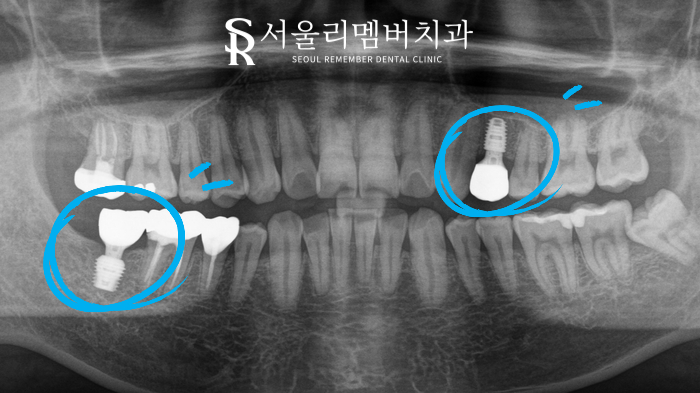

하악은 골의 양이 조금 부족하다 느껴

약간의 골이식과 함께

임플란트 즉시 식립을 해주었습니다.

반면에 상악은 골의 양이 충분하다고 판단하여

골이식을 진행하지 않았습니다.

3개월 정도의 회복 시간을 가진 뒤

위에 최종 보철물을 올려주었습니다.

환자분께선 심미적인 이유로

지르코니아 재료를 선택하셔서

최대한 치아 색에 맞춰 진행하였습니다.

치료 후

그렇게 모든 치료가 마무리되었는데요.

환자분께서도 만족해하시며

임플란트에 대한

고정 관념을 버리게 되었다고 하시더라고요.